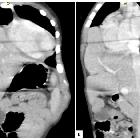

Unusual

association of parvo-virus with Morgagni hernia, mistaken for patch of consolidation. Coronal (A) and Sagittal (B) reformatted images showed herniation of LT lobe of liver along with vasculature into the RT sterno-costal space with shifting of heart towards LT side.